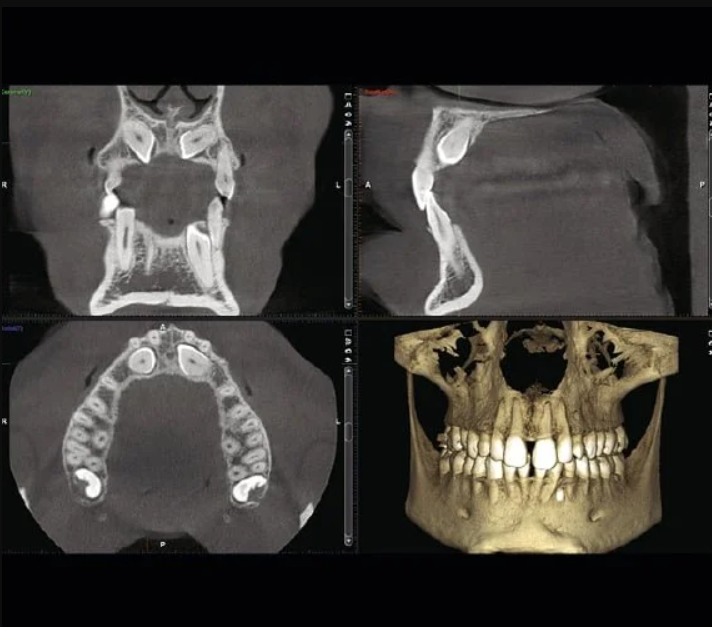

The CBCT system at Nova Dental Hospital generates sub-millimetre accuracy images in three anatomical planes simultaneously: axial (top-down), coronal (front-facing), and sagittal (side profile). This multi-plane view is what enables our specialists to plan surgeries and implant placements with extraordinary precision.

What Can CBCT Reveal That OPG Cannot?

A CBCT 3D scan goes far beyond surface-level imaging. It reveals:

- Bone volume and density — exact three-dimensional measurements of available bone for implant placement

- Nerve canal mapping — the precise location of the inferior alveolar nerve to prevent surgical damage

- Root morphology in 3D — curved, fused, or extra roots invisible in 2D

- Hidden infections — small periapical lesions and abscesses not visible on OPG

- Impaction depth and angle — exact position of wisdom teeth or unerupted canines relative to adjacent structures

- Sinus floor anatomy — critical for upper jaw implant planning near the maxillary sinus

- TMJ disc position — 3D evaluation of joint space and bone changes

- Airway assessment — identifying airway narrowing related to sleep apnoea